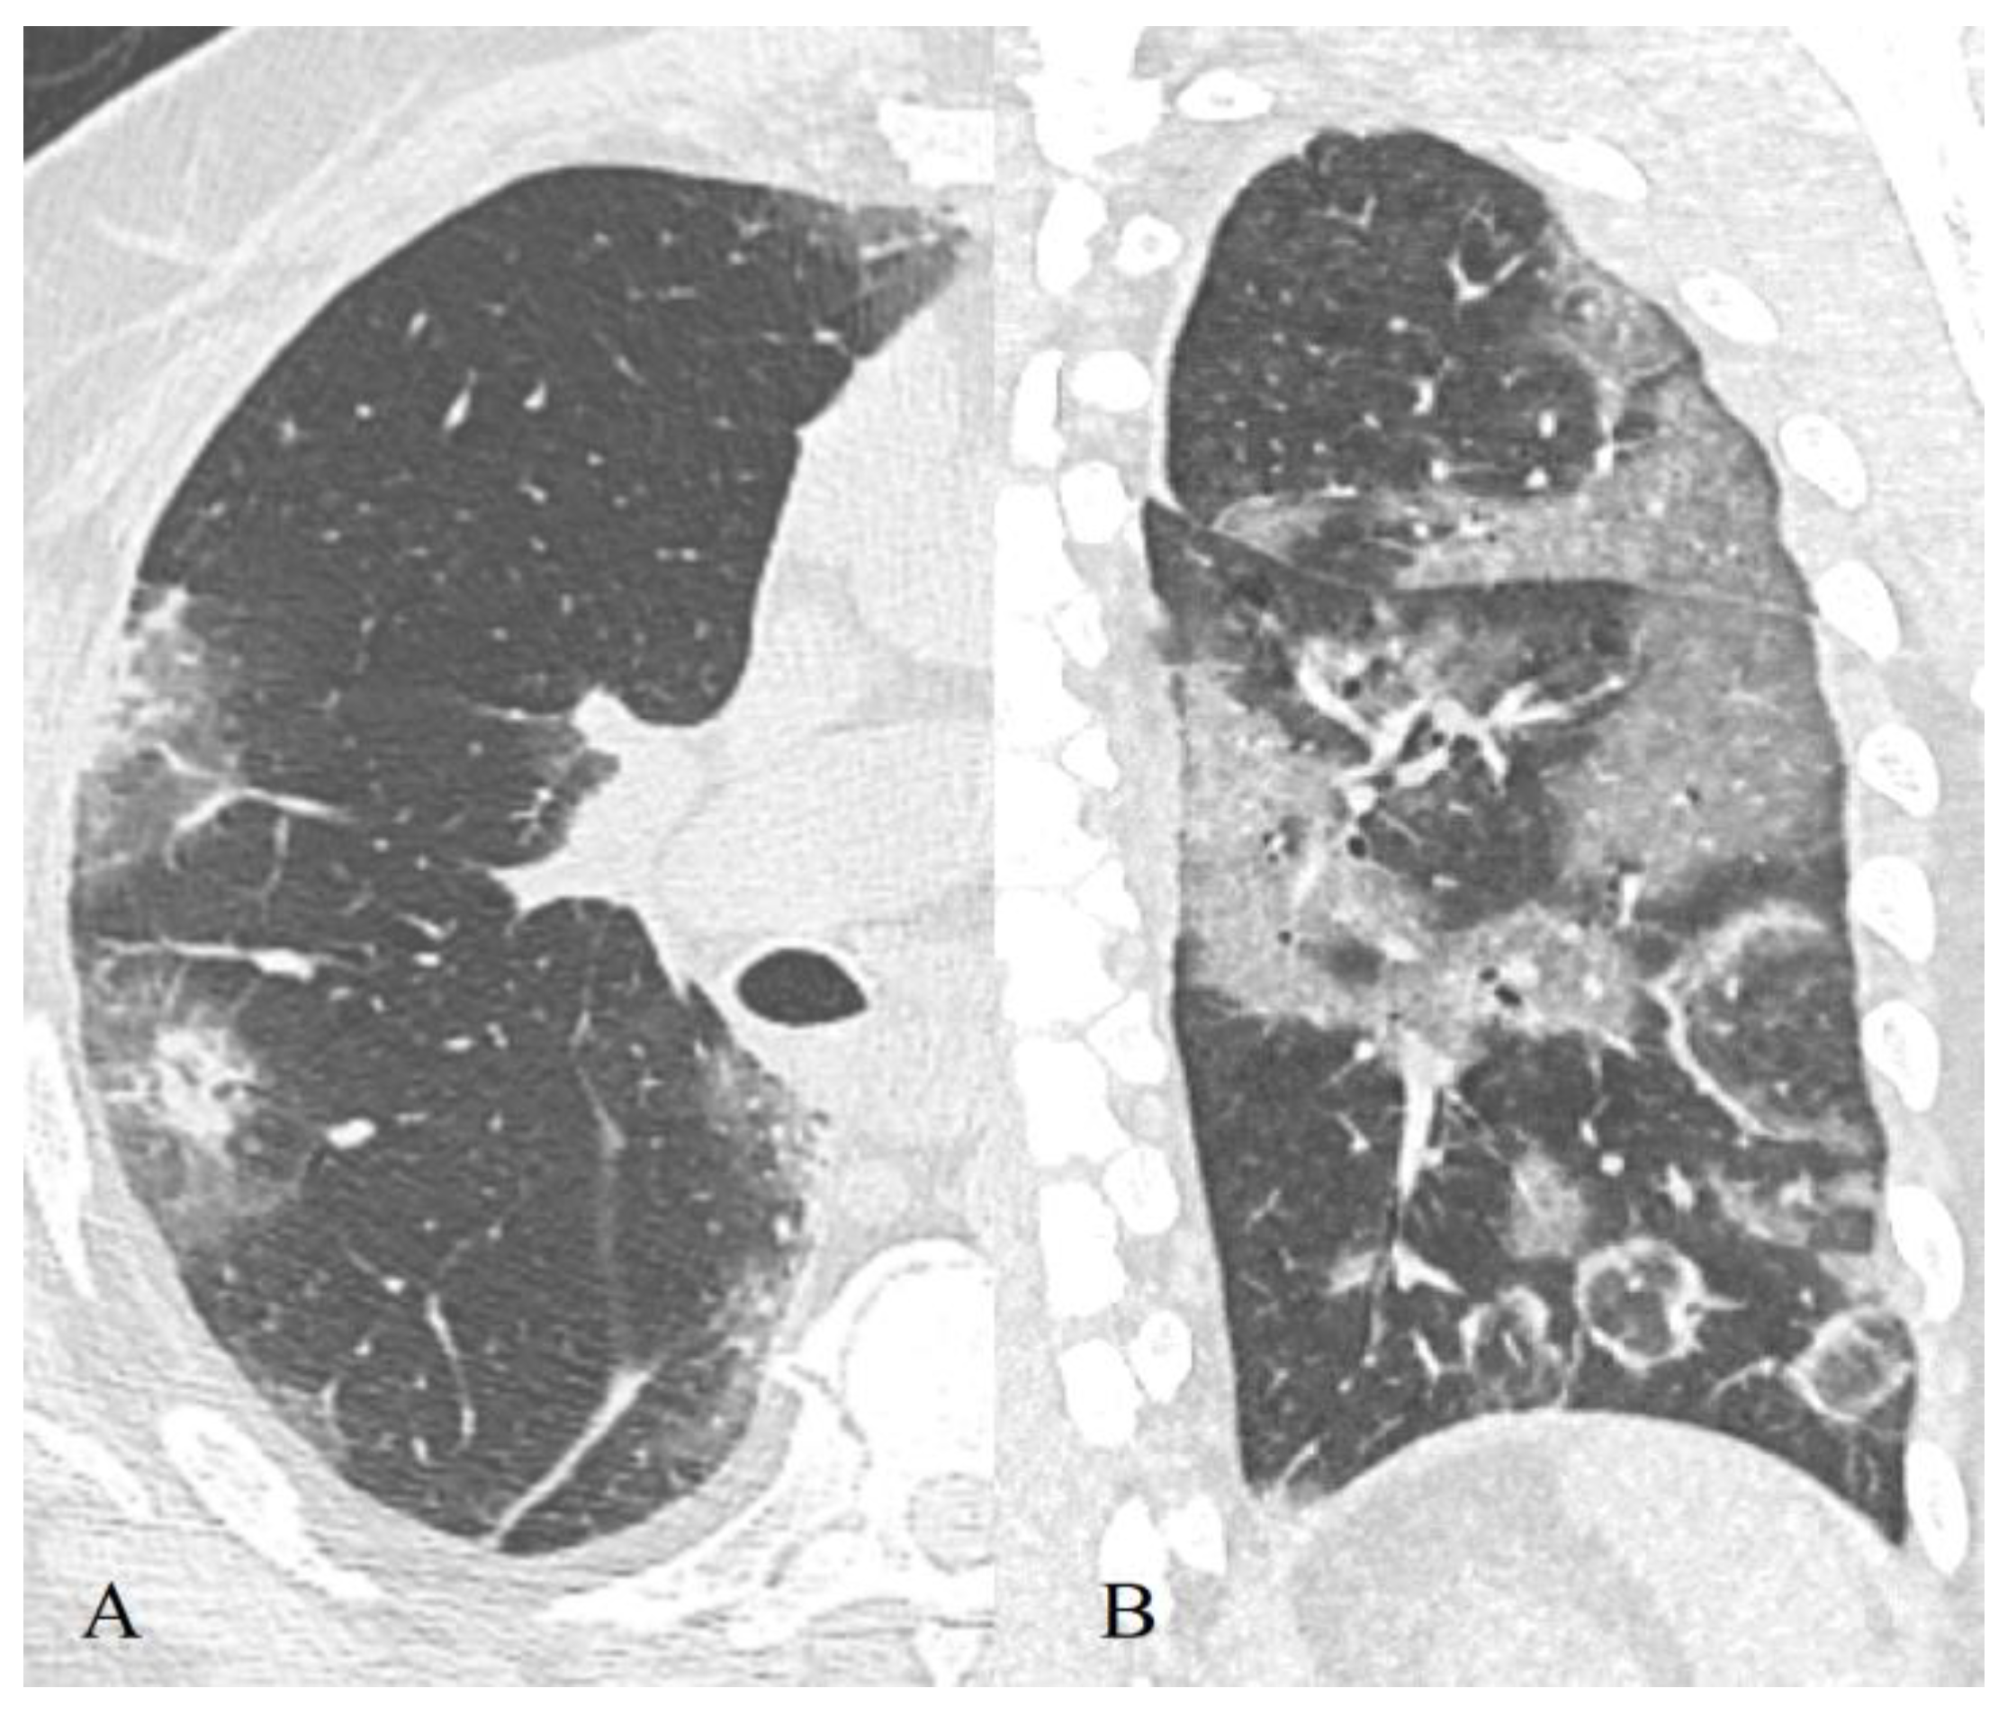

3.2.1. Ground-Glass Opacity

3.2.3. “Crazy Paving” Pattern